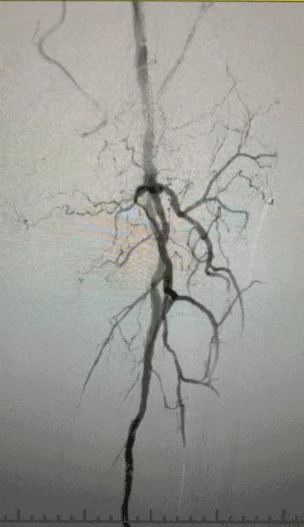

・術前イメージング: 両側下肢動脈における重度のびまん性石灰化狭窄症

複雑な血管状態を考慮して、ThorCrack末梢IVLバルーン拡張カテーテルシステムを選択しました。 患者の耐性が限られているため、両方の下肢に段階的な介入手順が実行されました。

外科的成果

処置後、動脈狭窄は大幅に改善し、血流が増加し、皮膚の温度が上昇しました。 術後の合併症は発生しませんでした。 患者と外科チームの両方が結果に非常に満足していました。